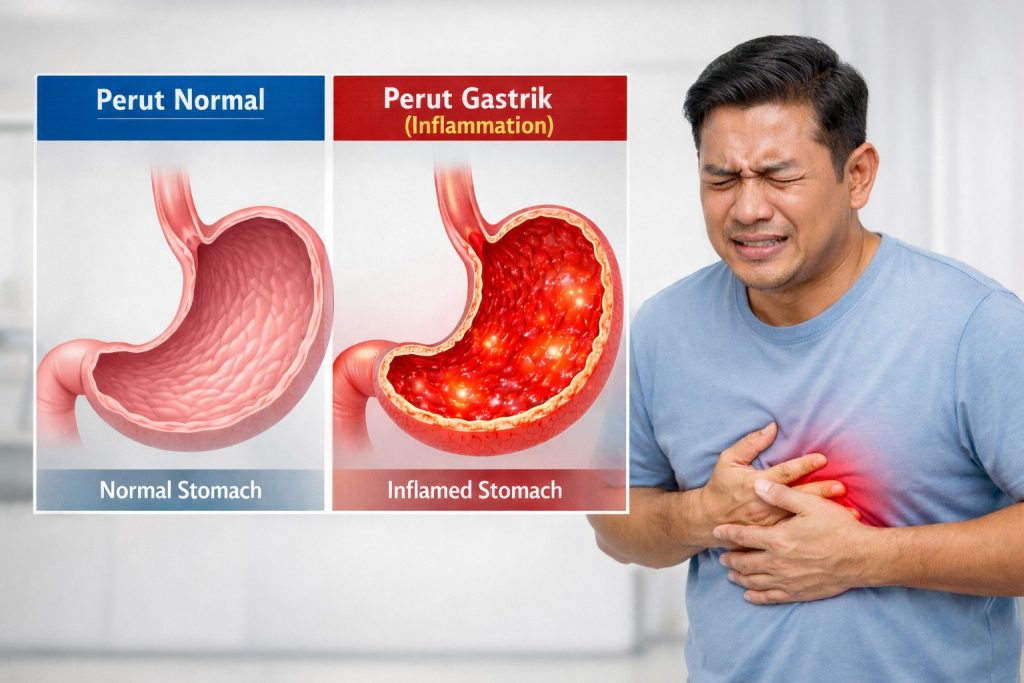

Lapisan pelindung perut yang menipis menyebabkan keradangan pada dinding perut akibat tindakblasa dengan asid perut.

Ini ialah dinding perut menipis dan membengkak akibat lapisan pelindung menipis dan tidak dapat melindungi dari asid perut.

ini gambaran perut yang sihat dengan perut yang tidak normal

Lapisan pelindung perut yang sihat akan melindungi perut dari terkena asid perut yang kuat

Nota : asid perut diperlukan untuk penghadaman dan bunuh kuman dalam perut. Asid perut bukan masalah, tapi lapisan pelindung perut yang menipis itu masalah sebenar.